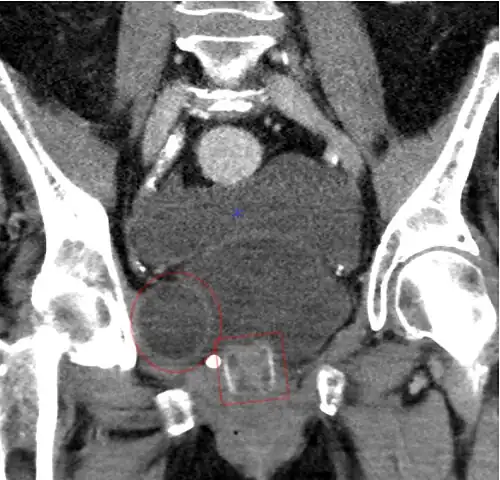

Tomografia computadorizada (reconstrução coronal) mostrando um AMS 800 em uma mulher.

Tomografia computadorizada (reconstrução coronal) mostrando um AMS 800 em uma mulher. -